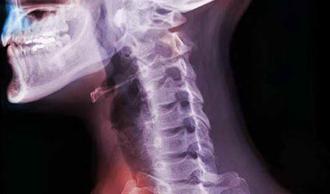

espondilosis vértebra

Se trata de la rotura de la lámina de la vértebra, de forma que la articulación facetaria queda separada del resto. Es un trastorno que afecta a las vértebras ¿los huesos que componen la columna. Aparecen pequeñas grietas en las vértebras (en las láminas) como consecuencia de las tensiones que soportan. La espondilosis suele producirse en las vértebras de la parte inferior de la columna. Algunas personas nacen con este trastorno, mientras que otras lo desarrollan como consecuencia de las tensiones que soportan sus vértebras cuando practican deporte.